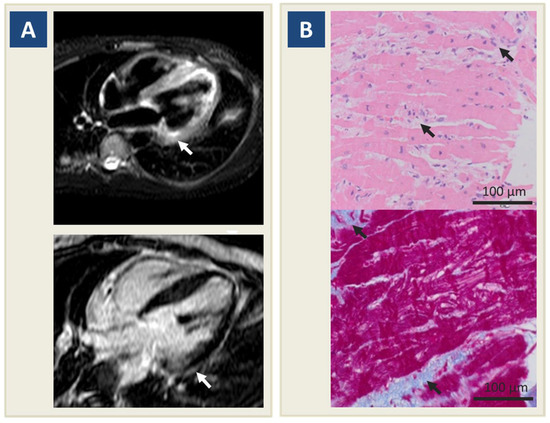

2. Case Report